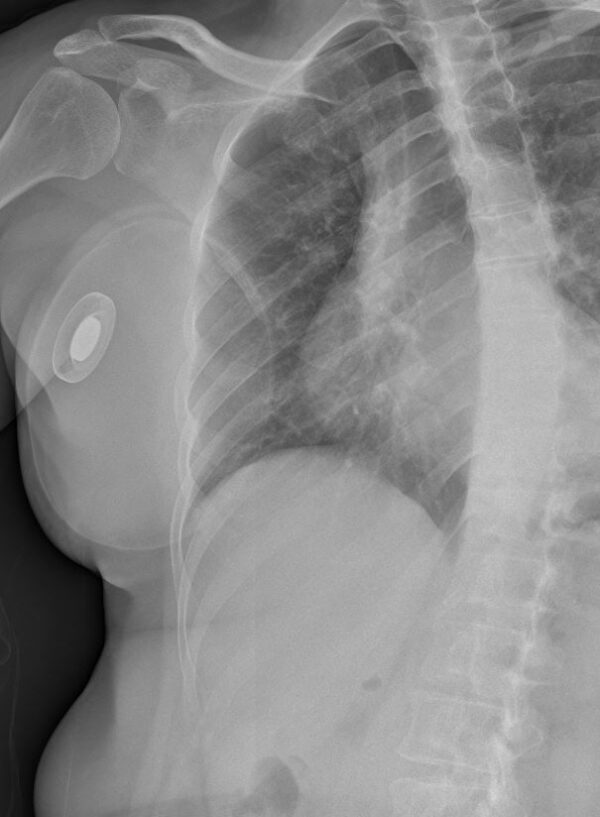

From www.svuhradiology.ie

Mastectomy CXR Radiology at St. Vincent's University Hospital Chest Expander After Mastectomy After mastectomy, your care team may use a breast tissue expander to ensure there’s enough room to reconstruct your new breast. After each expansion, you may feel some tightness and fullness in your reconstructed breast. After a mastectomy, tissue expanders can be used during immediate or delayed breast reconstruction to stretch the breast skin and chest muscle in order to. Chest Expander After Mastectomy.